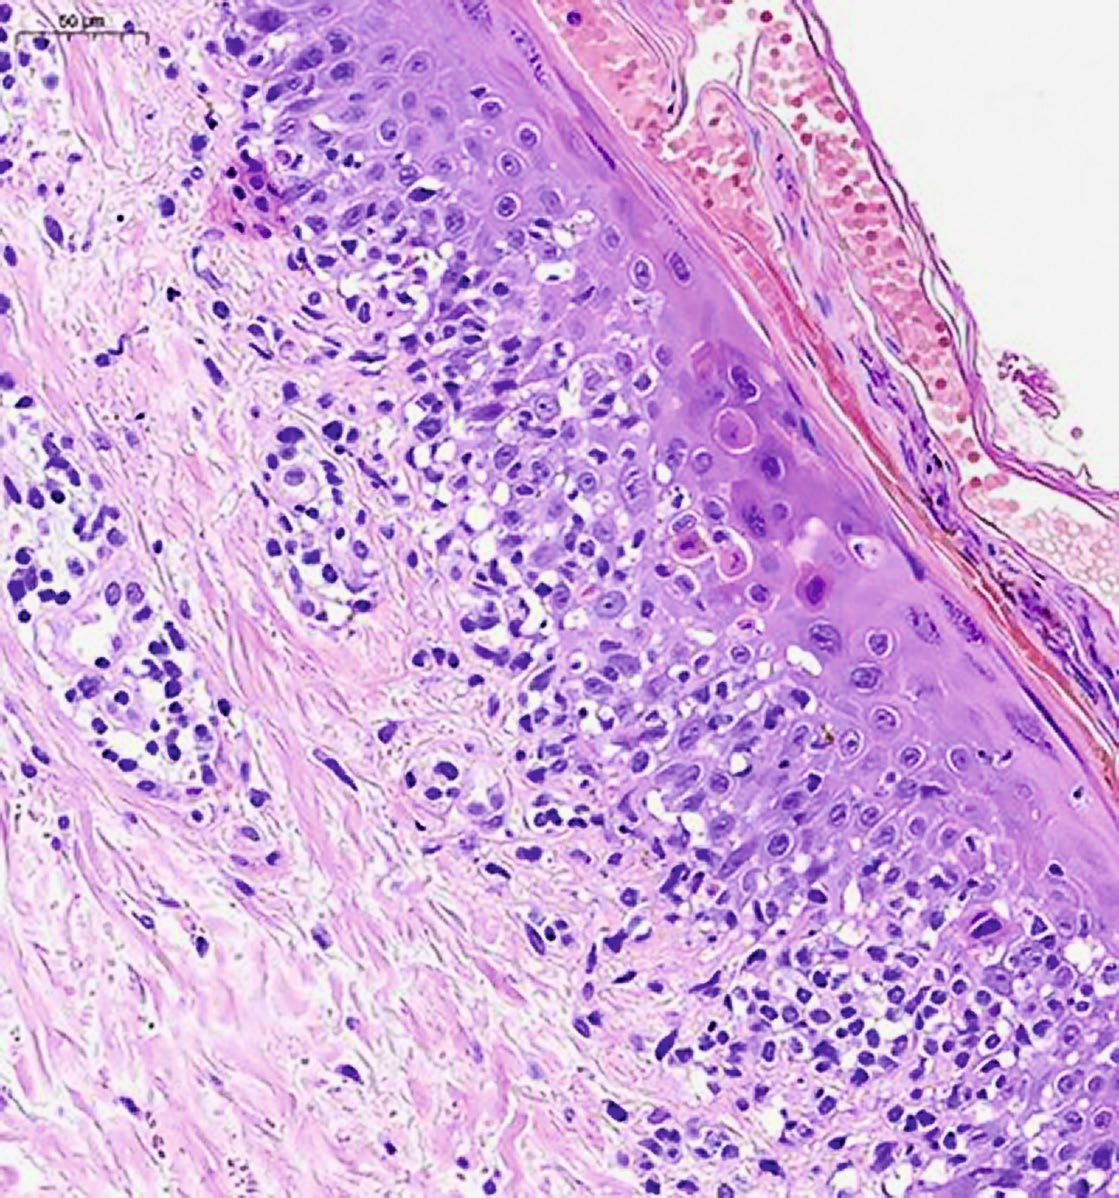

При гистологическом исследовании фрагмента кожи с окраской гематоксилином и эозином выявлен эпидермис с нерегулярным слабо выраженным акантозом, признаками чередования участков пара- и ортокератоза, перифолликулярными участками паракератоза, корками на поверхности, фолликулярными кератиновыми пробками (рис. 2). В верхних слоях дермы обнаруживается периваскулярный лимфогистиоцитарный инфильтрат с участками выраженного эпидермотропизма, в проекции которых эпидермис демонстрирует выраженный спонгиоз (рис. 3), признаки вакуольной дистрофии, содержит многочисленные тельца Сиватта (рис. 4). Среди клеток инфильтрата видны мелкие фрагменты коллагеновых волокон. Кровеносные сосуды сосочкового слоя дермы расширены, придатки кожи сохранены.

Рис. 3. Периваскулярный лимфогистиоцитарный инфильтрат дермы, окраска гематоксилином и эозином, ×200

Рис. 4. Тельца Сиватта в эпидермисе, окраска гематоксилином и эозином, ×200